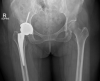

Delayed Femoral Artery Occlusion After Total Hip Arthroplasty via the Posterior Approach: A Single-Case Report From Thailand

Arterial injury after total hip arthroplasty is rare, but the consequences of this complication are serious and potentially life-threatening. Here, we report a case of delayed-onset common femoral artery occlusion after total hip arthroplasty that was performed via the posterior approach at Siriraj Hospital-Thailand's largest university-based national tertiary referral center. Our case was successfully treated with arterial thromboembolectomy. We postulate that anterior retractor placement caused intimal injury to the vessel. Routine monitoring of postoperative vascular pulse is essential. Early detection and prompt vascular surgeon consultation are the important factors for preventing the potentially catastrophic consequences of this complication.